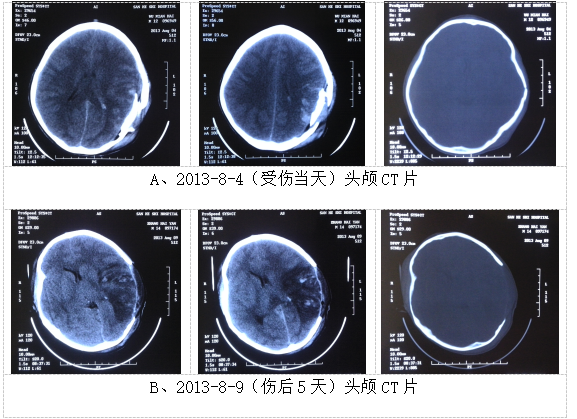

2013-8-4头颅CT片示:左侧颞、枕、顶骨骨质不连续,左侧顶骨游离骨块向内塌陷,局部脑组织向外膨出;左颞顶叶局部可见高密度灶、密谋不均匀,左外侧裂池密度增高,左侧侧脑室轻度受压,中线结构尚居中;左颞顶枕部头皮下软组织肿胀、密度增高。(见附件4-A)

2013-8-9头颅CT示:左侧开颅术后,局部颞顶颅骨缺如,左颞顶枕叶脑水肿明显,其内兼以高密度影,左侧侧脑室受压,局部中线结构略右偏。(见附件4-B)

附件4:影像学资料扫描图片